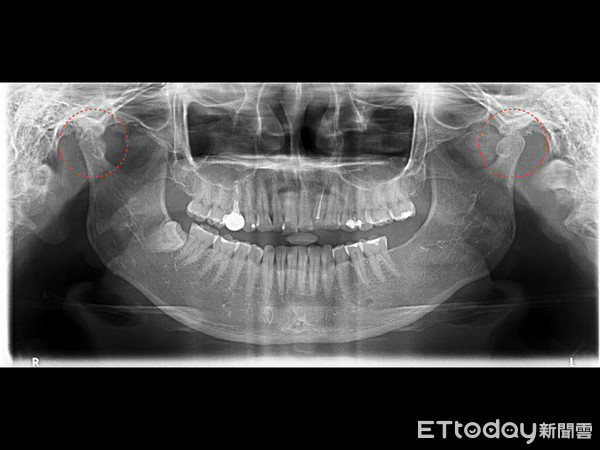

▲顳顎關節長期磨損不對稱。(圖/中壢天晟醫院提供)

黃小姐經診斷後發現顳顎關節已發炎變形,張、閉口不但有困難,用力張開關節還會發出聲響,咀嚼肌也因過度使用而緊繃僵硬,自覺臉型也變得越來越像「大餅臉」。楊梅天成醫院牙科部主治醫師徐偉軒表示,顳顎關節功能障礙(temporomandibular joint disorders, TMD),又稱顳顎關節症候群,發生原因很多,常見於咬合不正、夜間磨牙或緊咬牙關,以及飲食習慣不適當,如喜咬硬殼、軟骨,或肉乾、魷魚絲、波霸珍珠等Q彈有嚼勁的食物。

過度頻繁地咀嚼使得咬合肌肉緊繃、關節磨損,有異音或彈響,嚴重時有可能張口困難,或是下巴容易脫臼。喜歡大口啃雞腿、超大漢堡之類的動作也可能使顳顎關節系統受傷。若長時間習慣只以單邊咀嚼,更有可能產生兩邊咀嚼肌使用不平均而使臉型不對稱,變成大小臉。